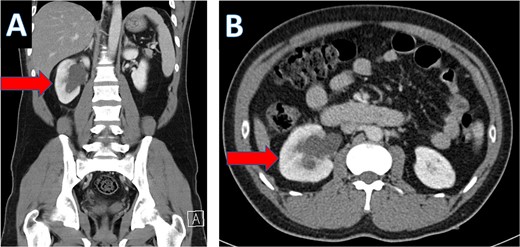

Multiple tiny obstructive stones were also noted bilaterally. The appendix measured approximately 1.4 cm in maximum caliber, with an appendicolith present within the appendiceal lumen (Fig. 3a). Significant surrounding fat stranding was noted around the appendix, and multiple enlarged lymph nodes with signs of reactive inflammation were seen adjacent to the cecum (Fig. 3b).

Coronal CT scan showing appendicolith (A) and axial CT showing appendicitis (B).